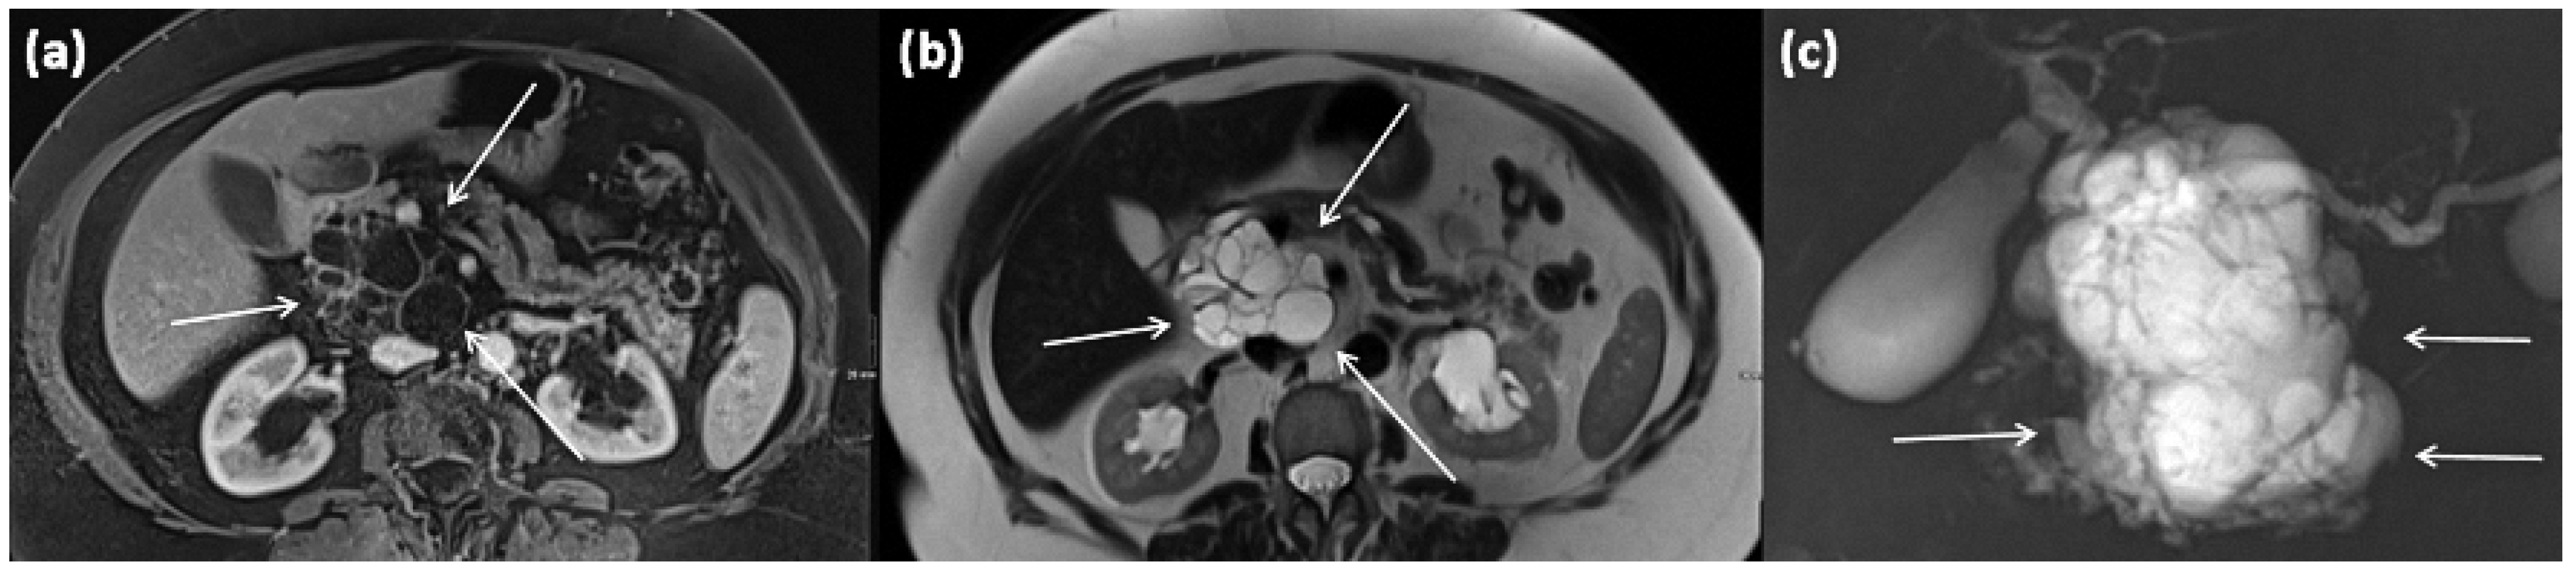

Changes occur within the side branches of the pancreatic duct (Figure 11 and Figure 12), often in the area of the uncinate process. In many cases, multiple branch ducts are affected in the sense of a multifocal IPMN, which is present in up to 30% of cases []. In this case, each individual cystic lesion must be analyzed separately on imaging for signs of malignancy (grade 2C recommendation) []. Typically, a flask-like or grape-like configuration (“grape-like appearance”) is seen. It is often difficult to differentiate a solid tumor formation due to the only small size of an IPMN. To differentiate lateral duct IPMN from other mucinous tumors, such as MCN, evidence of a ductal connection should be obtained by MRCP or ERCP.

Figure 11.

Axial CT in portal venous phase (a) and axial MRI with T1w after gadolinium-based contrast administration (b) as well as T2w native (c) in a 64-year-old female patient. In the pancreatic body, a sharply demarcated, roundly configured, cystic lesion is present, fit to a branch duct IPMN (arrows). There are no main duct dilatation, solid parts, or vegetations. T2w shows a homogenous hyperintense signal.

Figure 19.

MRI of a 79-year-old female patient with axial T1w (a) after gadolinium-based contrast administration, T2w, and (b) magnetic resonance cholangiopancreaticography (MRCP) (c). A merging and communicating multicystic formation is seen at the head of the pancreas, with the single cystic parts showing marked differences in size. Septa show mild contrast enhancement. In T2w a homogenous hyperintense signal is present. The tumor is marked with arrows in all sequences.